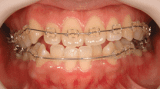

■症例1

Before

After